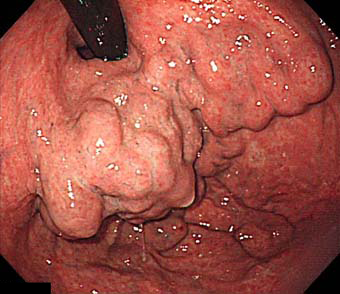

食道・胃静脈瘤の内視鏡所見

a:食道では数珠状に拡張した血管を認める。

b:胃噴門部・穹窿部では結節状の血管を認める。